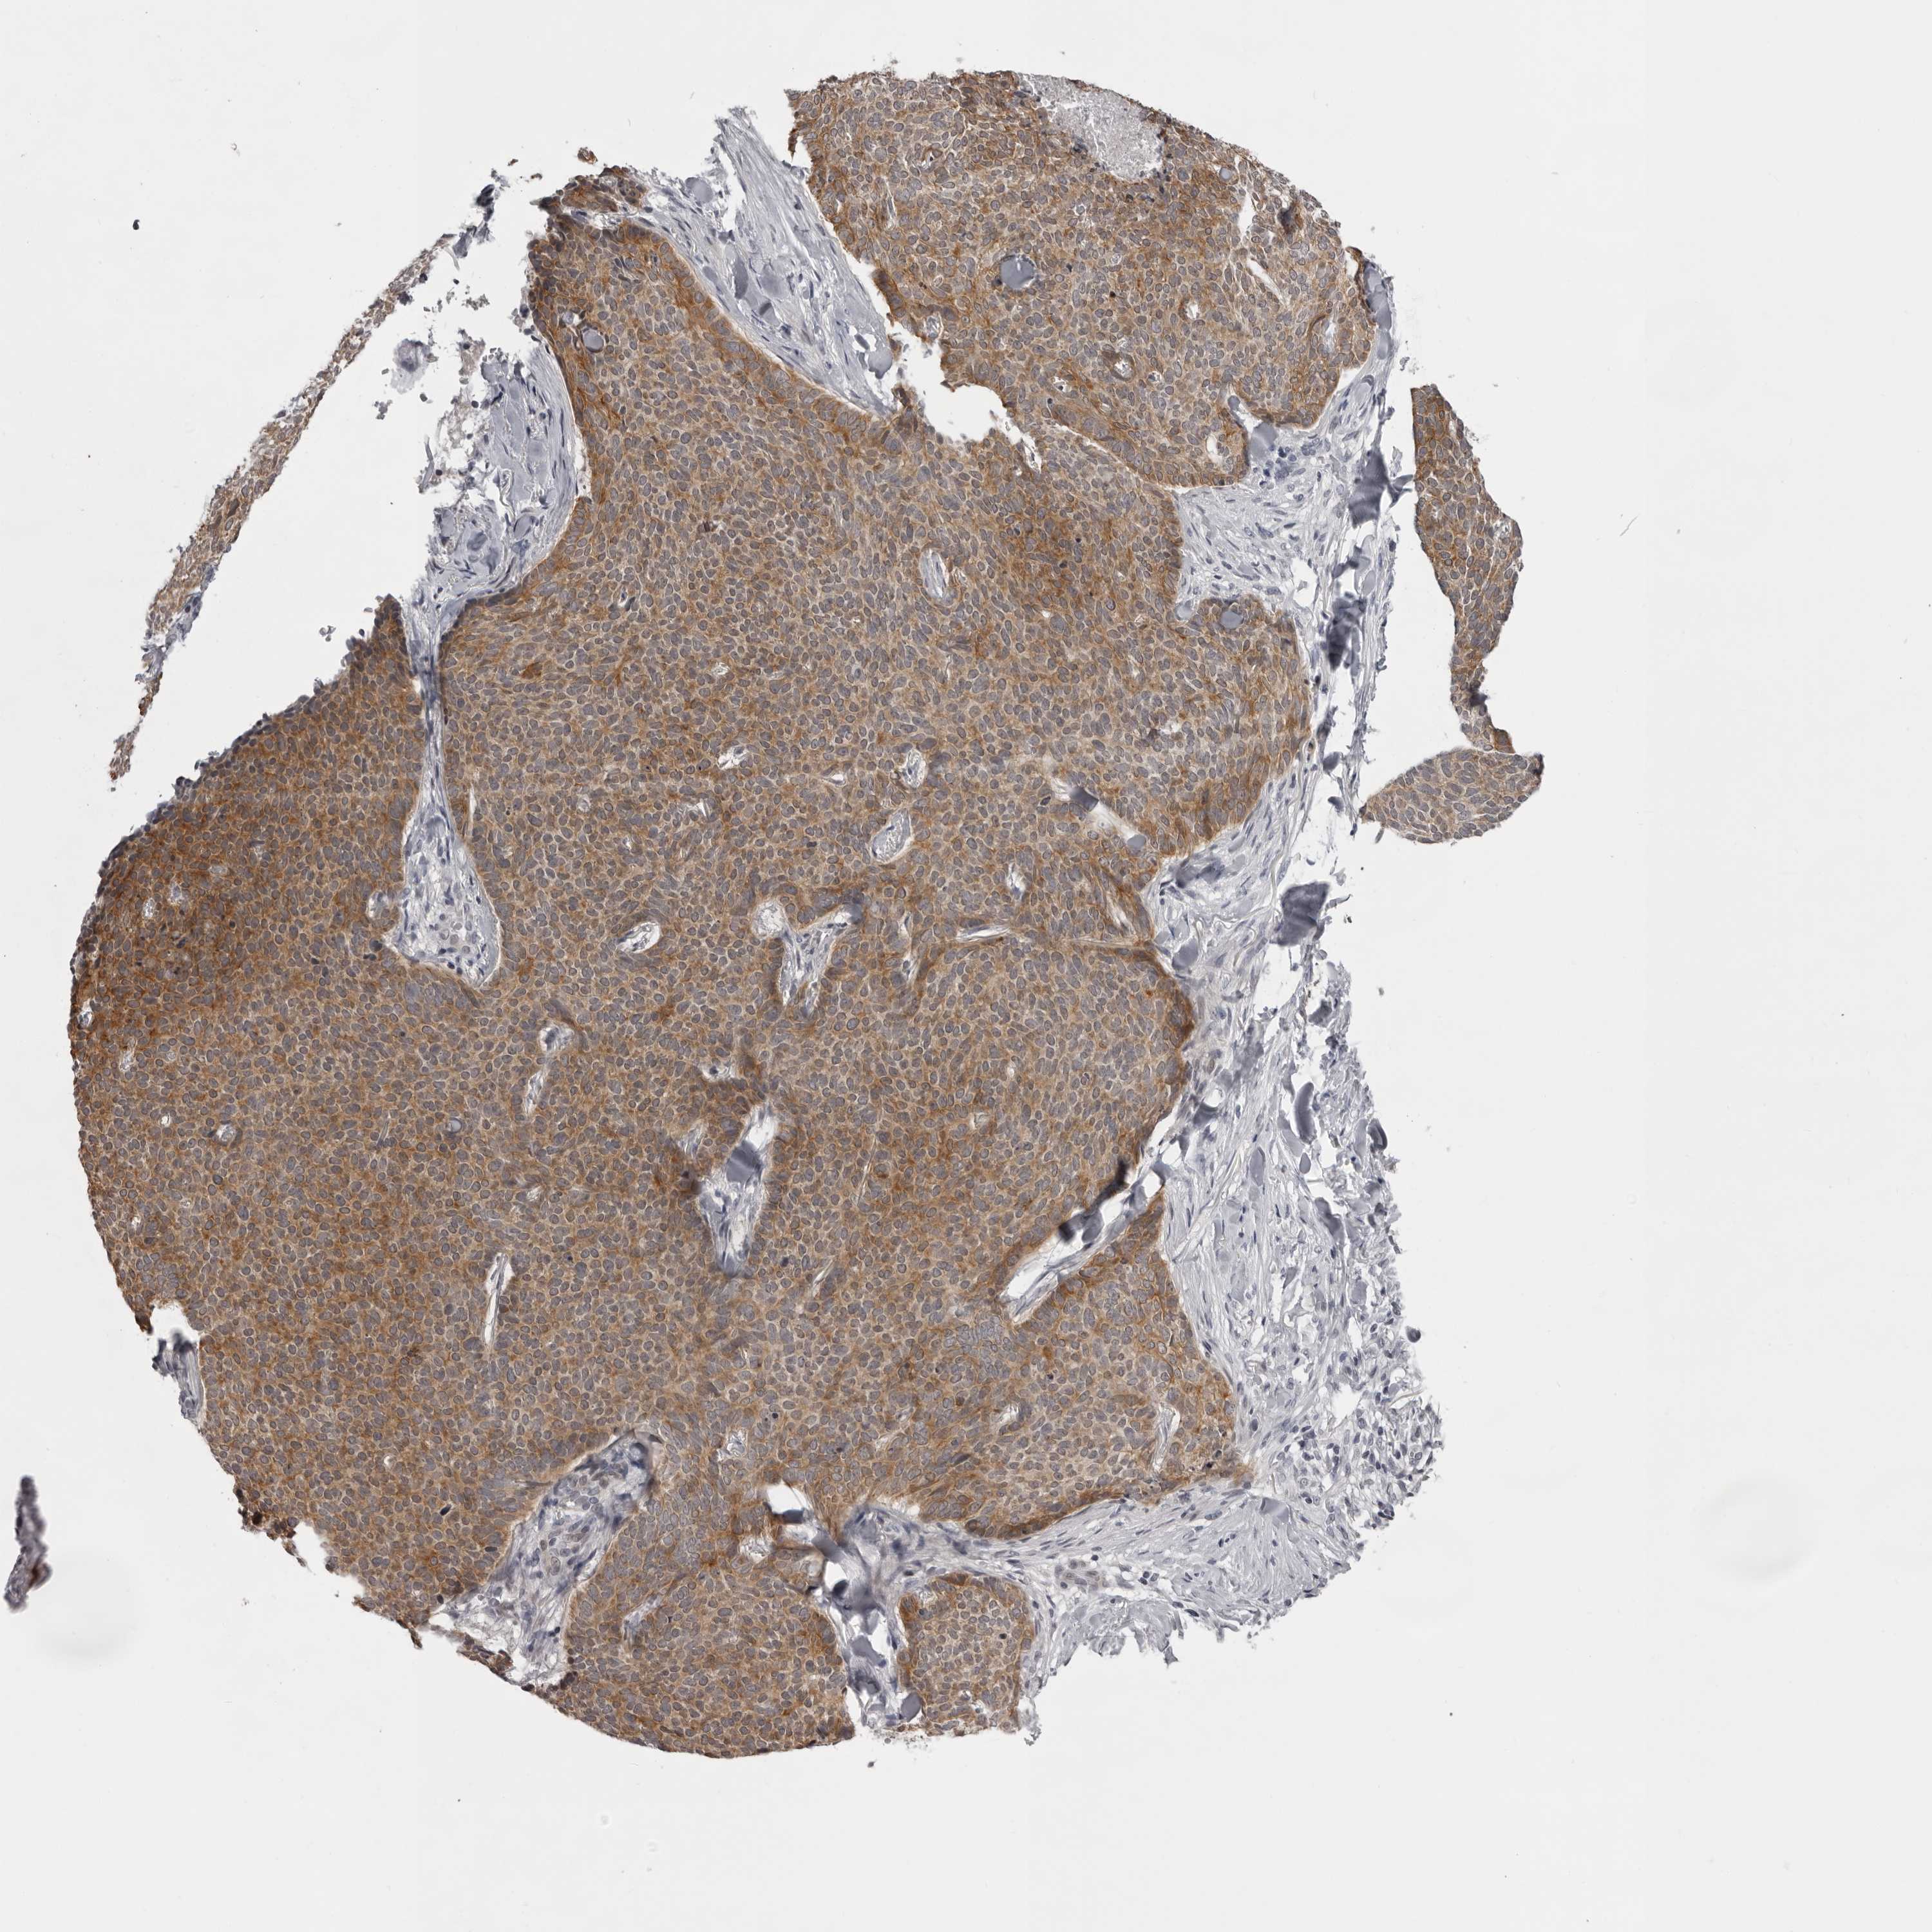

SKIN CANCER - Protein expressioni

A mouse-over function shows sample information and annotation data. Click on an image to view it in a full screen mode. Samples can be filtered based on level of antibody staining by selecting one or several of the following categories: high, medium, low and not detected. The assay and annotation is described here.

Each image is clickable and will lead to virtual microscopy that enables deeper exploration of all samples and also displays staining intensity scores, fraction scores and subcellular localization as well as patient and tissue information for each sample.

Antibody HPA028581

Staining

Medium

Intensity

Moderate

Quantity

75%-25%

Location

Cytoplasmic/membranous

Basal cell carcinoma